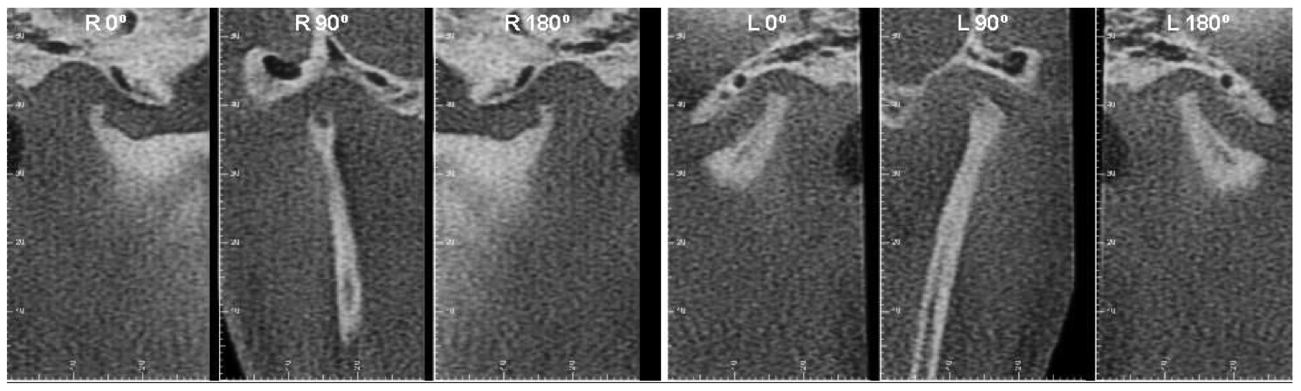

Exemplo de uma terapia - INFILTRAÇÃO GUIADA POR ULTRASSOM

Imagem Ricardo Tesch.